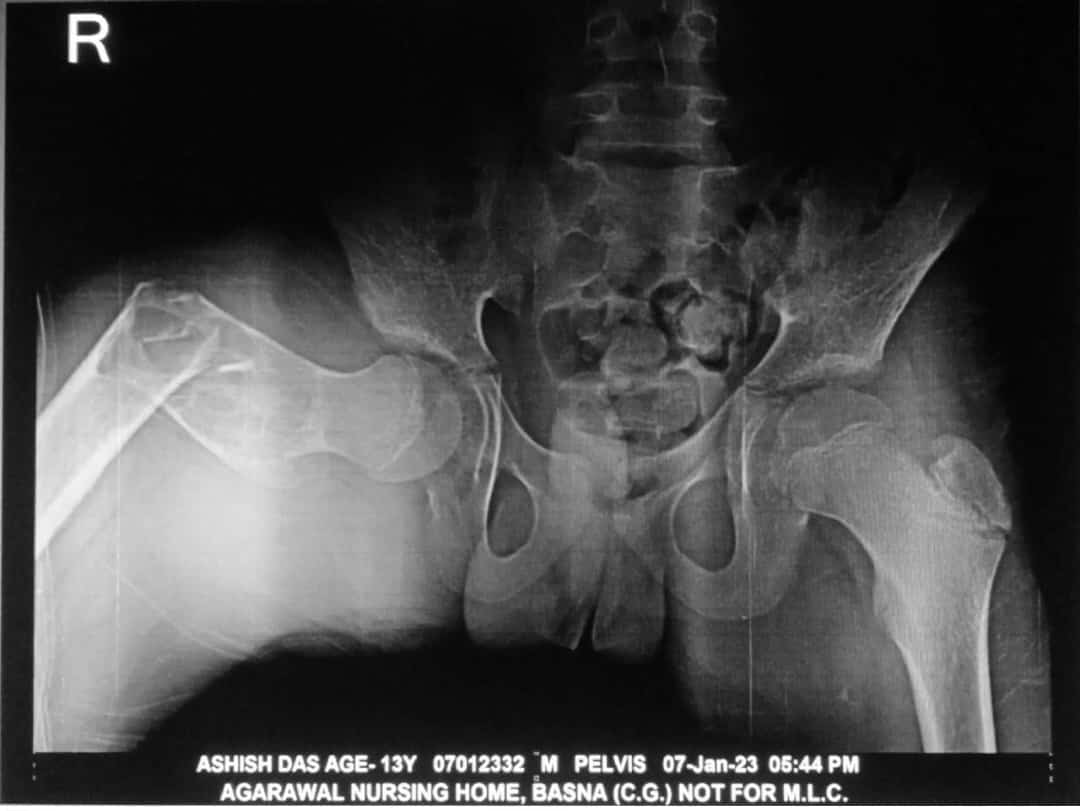

बसना स्थित अग्रवाल नर्सिंग होम में डॉ. खूबचंद बघेल स्वास्थ्य सहायता योजना’ सेआशीष दास का निःशुल्क ऑपरेशन किया गया। बसना ब्लॉक के ग्राम खटखटी निवासी 13 वर्षीय मरीज आशीष दास घर में फिसल कर गिर गया था जिससे दाये जांघ की हड्डी टूट गया जिसे बसना स्थित अग्रवाल नर्सिंग होम लाये जहाँ शिशु रोग विशेषज्ञ डॉ. अमित अग्रवाल,हड्डी रोग एवं जोड़ प्रत्यारोपण विशेषज्ञ डॉ. संदीप सराफ अग्रवाल ने ऑपरेशन की सलाह दिए.

अग्रवाल नर्सिंग होम के डॉक्टर्स ने सभी आवश्यक जांच के बाद मरीज के जांघ की आधुनिक विधि द्वारा ऑपरेशन किया गया। ऑपरेशन के दूसरे दिन ही मरीज अपने पैरों पर चलने में सक्षम हो गया।

मरीज को पांच दिनों तक अस्पताल में रखकर पूरा इलाज करने के बाद मुफ्त दवा देकर छुट्टी दी गई। साधारण मरीज को जहां इस इलाज और ऑपरेशन में 50 से 60 हजार रुपए लगते हैं, बसना अग्रवाल नर्सिंग होम में आयुष्मान कार्ड के तहत पूरा इलाज निःशुल्क किया गया।